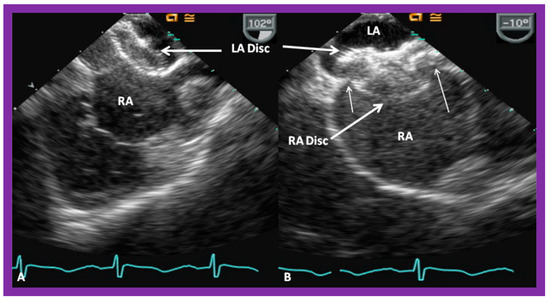

9.2. Device Position